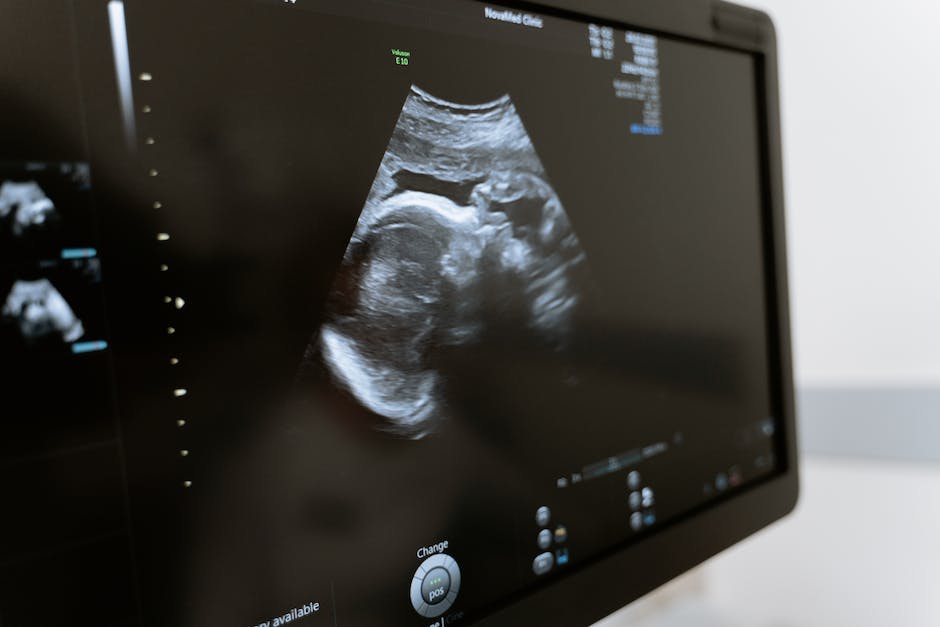

수원제일산부인과에서는 다양한 내시경 검사를 제공하고 있습니다. 내시경은 여성의 장기를 직접 관찰하면서 진단을 할 수 있는 검사 방법으로, 자궁내막암, 난소종양, 자궁근종 등의 질환을 정확하게 확인할 수 있습니다. 내시경 검사는 미세한 카메라와 소도구를 이용하여 진행되며, 불편한 증상을 유발하지 않습니다.

수원제일산부인과에서는 다양한 질환에 대한 정밀한 검사와 치료를 진행합니다. 여성들의 건강을 위해 자궁내막암, 자궁근종, 자궁경부암 등 다양한 질환을 진단하고 치료하는 서비스를 제공합니다. 의료진들은 최신 장비와 기술을 활용하여 정확한 진단과 치료를 진행하며, 여성들의 건강을 지키기 위해 최선을 다합니다.